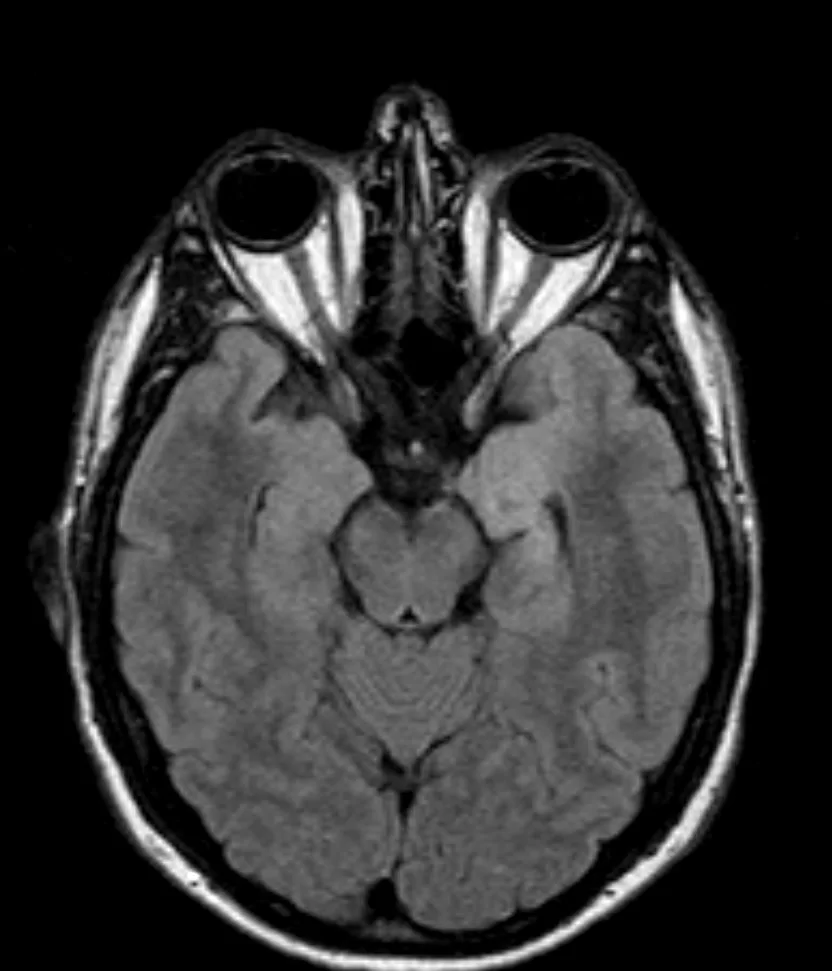

Αραχνοειδής Κύστη Εγκεφάλου

Ασθενής γυναίκα 58 ετών με πονοκεφάλους και διαταραχές όρασης. Ο οφθαλμολογικός έλεγχος έδειξε οίδημα οπτικών θηλών άμφω και σημαντικό περιορισμό των οπτικών πεδίων. Τα συμπτώματα